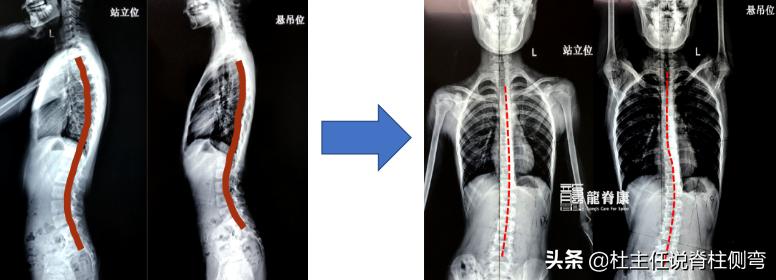

吊单杠站立位与悬吊位对比

通过上图我们可以清楚地看到,吊单杠后侧弯角度不仅没有减轻,甚至还增加了。这到底是为什么呢[what]脊柱侧弯是一个三维的畸形:①冠状面上,它不仅出现了脊柱左右的侧凸;